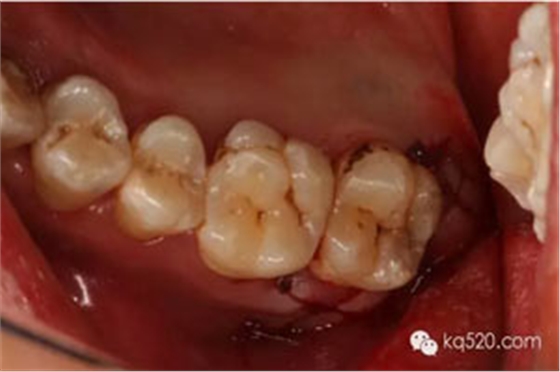

圖8.去骨后,可見28的牙冠,牙冠合面朝向遠(yuǎn)中水平。

徹底暴露28的牙冠和牙根。